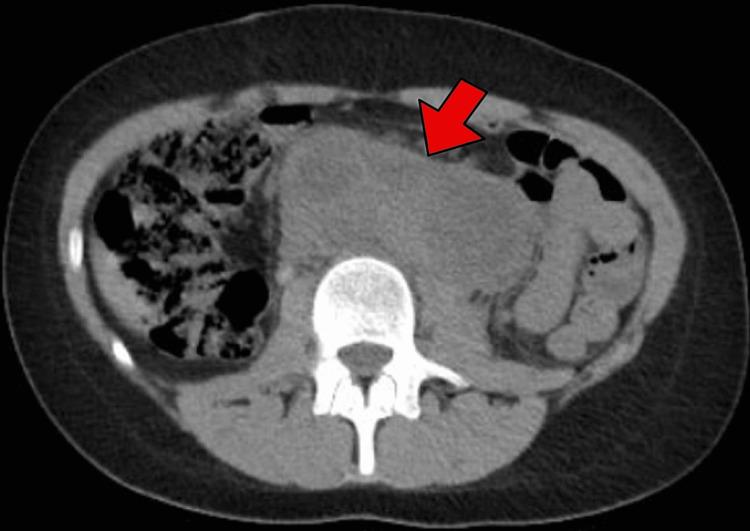

The 46,XY disorder of sexual development (DSD) is a rare congenital condition characterized by a 46,XY karyotype associated with complete or disturbed female gonadal development and a non-virilized phenotype. The presence of Y chromosome material in these patients' karyotypes increases the risk of germ cell tumor development. The present study reports a unique case of a 16-year-old phenotypically female patient presenting with primary amenorrhea, who was later diagnosed with 46,XY DSD. After bilateral salpingo-oophorectomy, the patient was diagnosed with stage IIIC dysgerminoma. The patient received four cycles of chemotherapy and showed a good response. The patient is currently alive and well, with no evidence of disease after the residual lymph node resection.

46,XY性发育障碍(DSD)是一种罕见的先天性疾病,其特征为46,XY核型,伴有完全或紊乱的女性性腺发育以及非男性化表型。这些患者核型中Y染色体物质的存在增加了生殖细胞肿瘤发生的风险。本研究报告了一例独特病例,一名16岁表型为女性的患者因原发性闭经就诊,后来被诊断为46,XY DSD。双侧输卵管卵巢切除术后,患者被诊断为IIIC期无性细胞瘤。患者接受了四个周期的化疗,反应良好。患者目前健在,残余淋巴结切除术后无疾病证据。